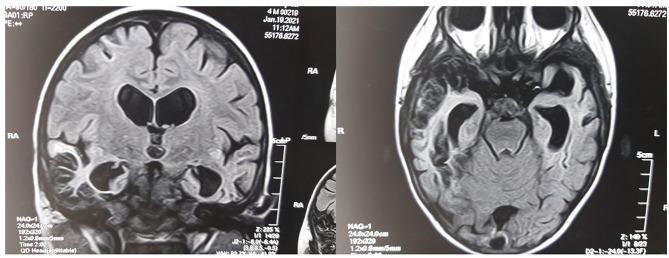

Fig. 2.

The MRI of the brain in FLAIR mode in coronary (left) and axial (right) projections in a child with ASD associated with GFCD. There are signs of bilateral atrophy and cystic gliosis changes in the temporal lobes of the cerebral hemispheres after bilateral temporal necrotic-hemorrhagic HSV-1-etiology encephalitis (the authors’ observation)

Note to Fig. 2. On the MRI of the child’s brain with ASD in the coronal projection (left) and horizontal projection (right) in FLAIR mode, the cystic-fibrotic transformation of both temporal lobes of the cerebral hemispheres is visualized as a result of the previously experienced partial necrotic-hemorrhagic encephalitis of the temporal lobe during early childhood, caused by HSV-1 (own observation).